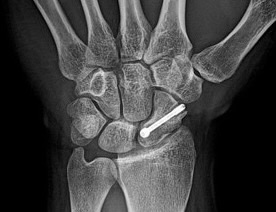

Surgery may be recommended if:

- The fracture is displaced (the bone has moved)

- It is located in a higher-risk area (closer to the wrist/proximal pole)

- There are concerns about healing

- The patient has risk factors (e.g. smoking, diabetes, vascular disease)

- A quicker return to activity is required (e.g. in athletes)

Surgery usually involves inserting a screw to stabilise the bone and promote healing.